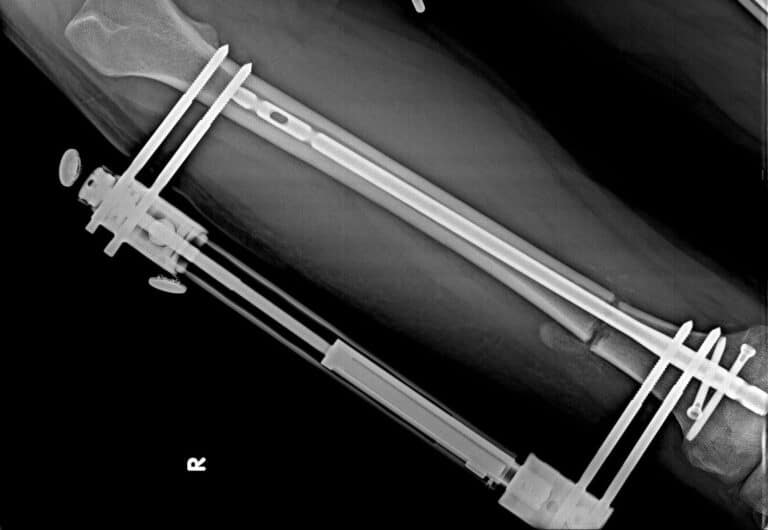

ما هي اضرار المسمار النخاعي؟